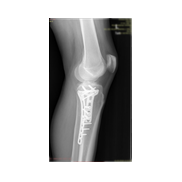

Görüntüleri büyütmek için resmin üstüne tıklayınız.